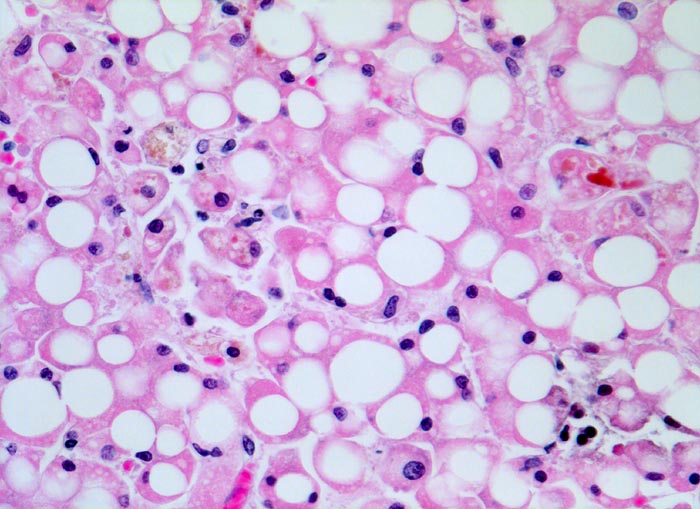

PathoPic – image database / PathoPic ID 4768 - grobtropfige Verfettung und hepatocanaliculäre Cholestase

grobtropfige Verfettung und hepatocanaliculäre Cholestase

Überwiegend grobtropfig verfettete Hepatozyten. Im Zytoplasma einzelner Hepatozyten und in einem Canaliculus ist gelbes Gallepigment nachweisbar.

Die hepatocanaliculäre Cholestase ist völlig unspezifisch. Sie kann wie im vorliegenden Fall bei einer Sepsis oder beispielsweise als Arzneimittelnebenwirkung auftreten. Intrazytoplasmatische Galle ist manchmal kaum von Lipofuszin oder Hämosiderin unterscheidbar. Die in den Gallecanaliculi zwischen zwei Hepatozyten gelegene Galle ist jedoch aufgrund ihrer Lage einfach als Cholestase identifizierbar.